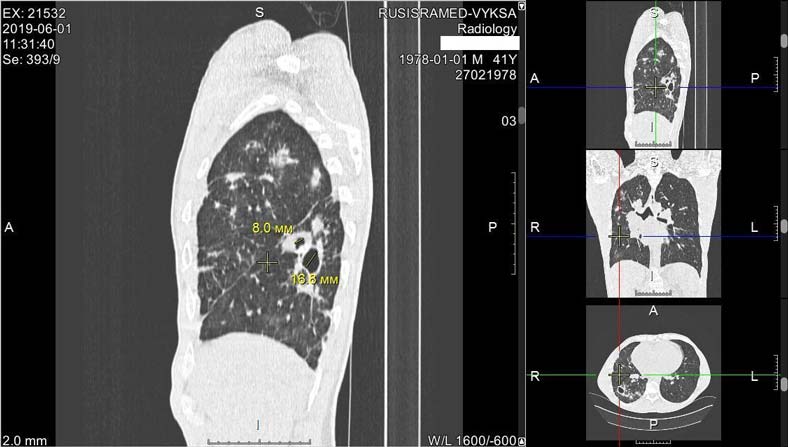

01.06.2019 пациенту проведена мультиспиральная компьютерная томография органов грудной клетки. Заключение: компьютерно-томографические признаки инфильтративного туберкулёза правого лёгкого в фазе распада (рис. 1). Лимфаденопатия средостения (рис. 2), генез под вопросом, туберкулёз бронха под вопросом, сочетание с раком лёгкого под вопросом.

Рис. 1. Мультиспиральная компьютерная томограмма органов грудной клетки. Снимки пациента от 01.06.2019: деструкция лёгочной паренхимы в нижней доле правого лёгкого